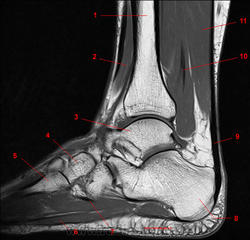

Рис. 15

1, Длинный разгибатель пальцев. 2, Малоберцовая кость. 3, Пятая плюсневая кость. 4, Четвёртая плюсневая кость. 5, Мышца, отводящая мизинец стопы. 6, Длинная малоберцовая мышца.